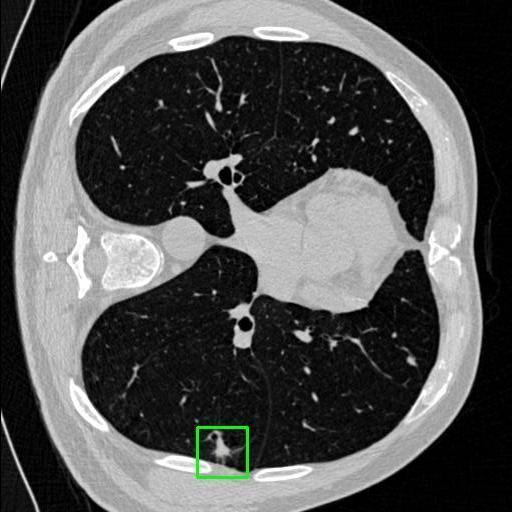

We developed an AI-based system using deep learning models for analyzing lung CT scans to detect and classify pulmonary nodules. We chose the YOLOv11 architecture for its enhanced object detection capability and adapted it specifically for medical imaging, incorporating pixel-level precision and severity classification.

Classification into three severity levels with colored bounding boxes.

Successfully built and deployed an AI model (YOLOv11) capable of detecting lung nodules in CT scans with high accuracy and real-time performance.

Designed a severity classification system that categorizes nodules into null, moderate, and severe using colored bounding boxes, assisting in rapid clinical decision-making.